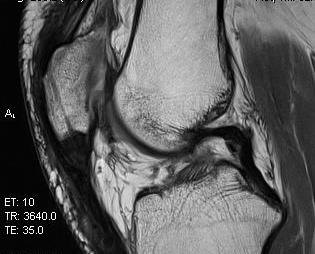

MRI

In chronic cases may only detect that tendon not attaching to distal pole patella